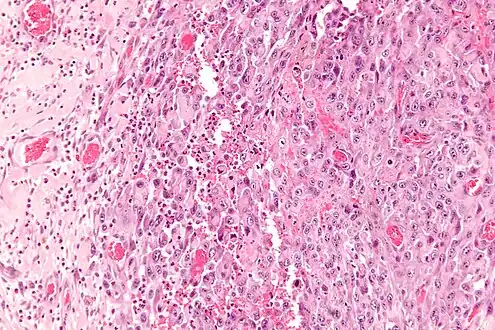

| Micrograph of an epithelioid sarcoma. H&E stain. | |

Histologically, epithelioid sarcoma forms nodules with central necrosis surrounded by bland, polygonal cells with eosinophilic cytoplasm and peripheral spindling.[3] Epithelioid sarcomas typically express vimentin, cytokeratins, epithelial membrane antigen, and CD34, whereas they are usually negative for S100, desmin, and FLI1 (FLI-1).[3] They typically stain positive for CA125.[4]

Intermed. mag. -

High mag. -

High mag. (SMARCB1)